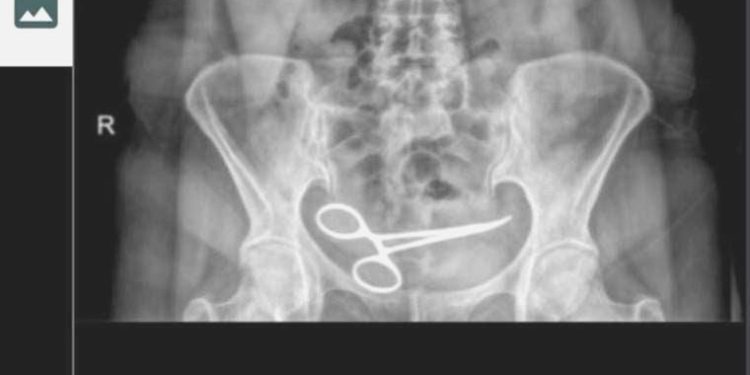

Karnında makas unuttular: 8 ay sonra fark edildi!

Ankara’da Şadiye Boyun, 28 Aralık 2021 tarihinde Pursaklar ilçesinde, özel hastanede bir bayan hastalığı nedeni ile ameliyat oldu. Ameliyattan 8 ay sonra karın ağrısı şikayeti görülen Boyun, ambulans ile Pursaklar Devlet Hastanesi’ne kaldırıldı. Burada çekilen röntgende Boyun’un ince bağırsağına takılı 12 santim uzunluğunda makas olduğu görüldü. Akabinde argümana nazaran, ameliyatın gerçekleştirdiği özel hastaneye haber verildi. Özel hastaneden vazifeliler geldi.

Görevliler tarafından tekrar özel hastaneye götürülen Boyun’un röntgeni çekildi. Bunun üzerine oğlu Fatih Boyun, durumdan şüphelenerek e-Nabız uygulamasından röntgen sonuçlarına baktı ve annesini Gülhane Eğitim ve Araştırma Hastanesi’ne sevk ettirdi. Şadiye Boyun’un karnındaki makas ameliyatla alındı. Boyun, avukatı aracığıyla, ameliyatı gerçekleştiren tabip ve hastane hakkında cürüm duyurusunda bulundu.

“RÖNTGENDE BANA ‘CEBİNDE MAKAS MI VAR’ DİYE SORDULAR”

Şadiye Boyun, yapılan yanılgı nedeniyle büyük mağduriyet yaşadığını söyledi. Ameliyat olduktan yaklaşık bir ay sonra tabiplerin denetim maksatlı kendisine gün verdiğini söyleyen Boyun, güzelleşmeyi beklerken rahatsızlandığını belirterek, “Geçen yılı 5 Ağustos’ta sancılandım, ambulansı aradım. Ambulans beni Pursaklar Devlet Hastanesi’ne götürdü. Benden direkt röntgen istediler. Bana oradaki röntgeni çeken misyonlu, ‘Teyze senin cebinde makas mı var?’ diye sordu. Ben de ‘Oğlum ne makası, bende makas filan yok’ dedim. Üzerimi denetim etti ve ‘Sende makas var’ dedi. Beni direkt nezaret odasına götürdüler. Benden röntgeni isteyen hekim da oraya geldi lakin bana makas olduğunu söylemedi. Bana ameliyat olduğum hastaneyi ve tabibin ismini sordu. Sonra bana gelip, ‘Seni almaya gelecekler öteki hastaneden, masraf misin?’ diye sordu. Ben de o olayın şoku ile gittim” dedi.

“25 GÜN İÇERİSİNDE 2 SEFER AMELİYAT OLDUM”

Özel hastanede tekrar muayene edildiğini söyleyen Şadiye Boyun, “Ben de, ‘Neyim var’ diye sorudum. Bana ameliyat yerimin ödem ve apse yaptığını söylediler. Ben de içimde ödem değil makas olduğunu söyledim. ‘Niye makası saklıyorsunuz’ diye sordum. Beni çabucak odaya götürdüler. Sonra oğlum müdahale etti. Oğlum da palavra söylediklerini anlayınca benim röntgen sonuçlarımı istemiş. Sonuçları ona da vermemişler. Sonra oğlum da ambulans çağırdı. Gülhane Eğitim ve Araştırma Hastanesi’ne gittim. Orada o gece ameliyata alındım. Ameliyat hoş geçti lakin 3 gün sonra tekrar sıkıntılar başladı. Ben kalp hastası olduğum için verilen narkozlar bende yan tesir yapmış. Bir hafta sonra ben tekrar ameliyat oldum. 8 ay içinde 3 defa, 25 gün içinde ise 2 kez ameliyat oldum. Meselelerim bitmiş değil, tekrar doktora gidiyorum. Fakat bana bir sefer özel hastane tarafından dönüş yapıp, ‘Geçmiş olsun, biz bu yanılgıyı yaptık. Özür dileriz’ bile demediler. Bana yapılan diğerine yapılmasın. Ben bu işi sonuna kadar götüreceğim” sözlerini kullandı.

“ADALETE GÜVENİYORUZ”

Fatih Boyun ise “Pursaklar Devlet Hastanesi’ndeki tabip, anneme açıklama yapmamakla bir arada öteki hastanenin tabibini arayıp, ‘ilgilenin’ demiş. Onlar da özel araç yollayarak kendi hastanelerine götürmüşler. Kendi hastanelerinde annemi röntgen çekmek için aşağı indirdikleri sırada ben geldim. Başhekim de oradaydı. Ben başhekime, ‘Hocam durum nedir? diye sordum. Başhekim ameliyattan ötürü bir kan birikmesi olduğunu söyledi ve ‘Biz bunu boşaltacağız’ dedi. Ben bu durumdan şüphelendim ve röntgen sonucunu görmek istedim. Beni sekreterliğe gönderdi, sekreterlik ise 12 saate kadar röntgen sonucunun çıkacağını söyledi. Ben de e- Nabız’dan Pursaklar Devlet Hastanesi’nde çekilen röntgen sonucuna baktım ve o ortada makası gördüm. Ben orada konuşurken annemi odaya çıkardılar, ameliyata hazırlıyorlardı. Durumu fark edince ben hekimleri çıkardım odadan ve annemin üzerini giydirip hastaneden uzaklaştım. Ben toplumsal medyadan ameliyatı yapan doktora ulaştım. Röntgen sonucunu gönderdim ve ‘8 ay evvel yaptığınız ameliyat’ dedim ve öteki hiçbir şey yazmadım. Tabip, ‘Üzgünüm, olmuş bu türlü bir şey’ dedi. Sonradan tabip biraz kendini haklı çıkarmaya çalıştı. ‘Biz yalnızca ameliyatı yaparız, sayımı hemşireler yapar’ dedi. Lakin sonuçta yapılmamış bir şey var ortalıkta, materyaller sayılmamış. Tabip imza atmış. Bu benim sorunum değil. Şu an davamızı açtık, dava gününü bekliyoruz. Adalete güveniyoruz” diye konuştu.